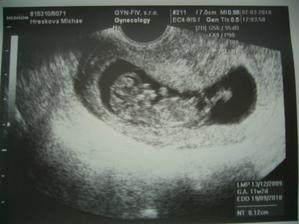

Boli sme u dokiny a fazulke bije srdiecko, aj sa hybala, asi zumbovala :D, aj prve vysledky z krvi su v poriadku. Tak sa tesime a dufame, ze vsetky dalsie vysetrenia dopadnu tiez dobre 🙂.

NT dopadlo dobre, boli sme este aj na krvi, ale vraj su to dielcie testy, kt. potom ukazu, ci je vsetko OK okolo 15tt -16tt.